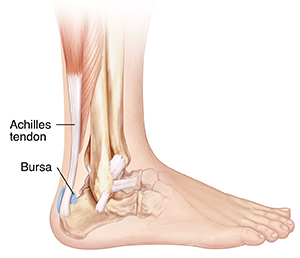

Retrocalcaneal bursitis is a condition that causes heel pain. This pain spreads from the bursa located between the Achilles tendon and the heel bone. This bursa normally provides a cushion as you walk.

A bursa is a fluid-filled sac. Your body has many of them. They are found in areas where rubbing may occur, such as between tendons and bones. The fluid inside them helps ease friction during movement. If they become injured or irritated, you may feel pain.